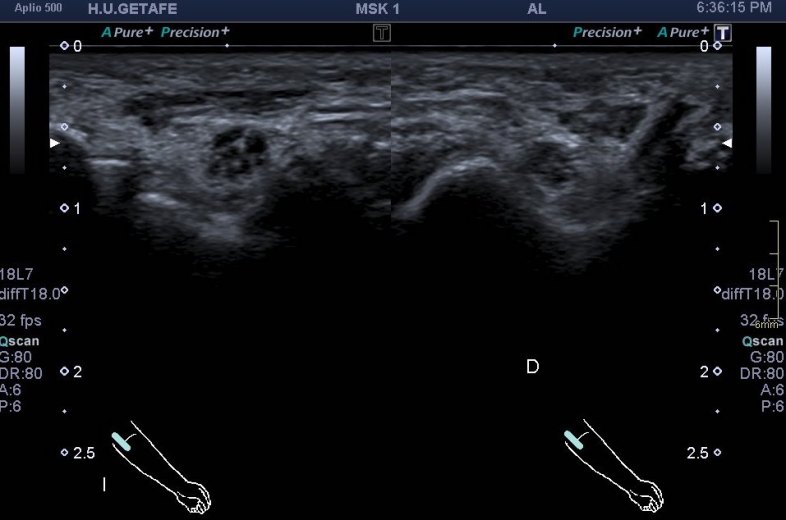

Ahora observa la siguiente imagen y compara:

Esta semana tenía que ser…una paciente con una sospecha de neuritis del cubital. Efectivamente en el corte idéntico al de la imagen superior, puedes ver un nervio muy aumentado de tamaño, desplazado, pero justo encima de él, superior y en forma de sombrero una imagen hipoecogénica alargada, con aspecto de músculo que no debiera estar ocupando ese espacio.

Siempre que tengas la oportunidad debes de usar el lado contralateral para salir de dudas…mira que imagen más preciosa vas a ver ahora, de ambos canales del cubital. Comparativas:

Compara ambas localizaciones, ambos nervios, como cambia el aspecto del izquierdo en comparación con el derecho y como en este, en el derecho, no existe en músculo ancóneo apitroclear. Derecho normal, izquierdo patológico.